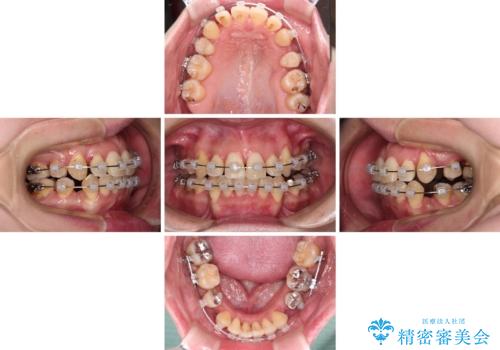

- クリアブラケット

- 2年9ヶ月

治療期間全体を通して歯の移動スピードがゆっくりであったので、当初予定よりも1年ほど長い、3年間を要することとなりました。